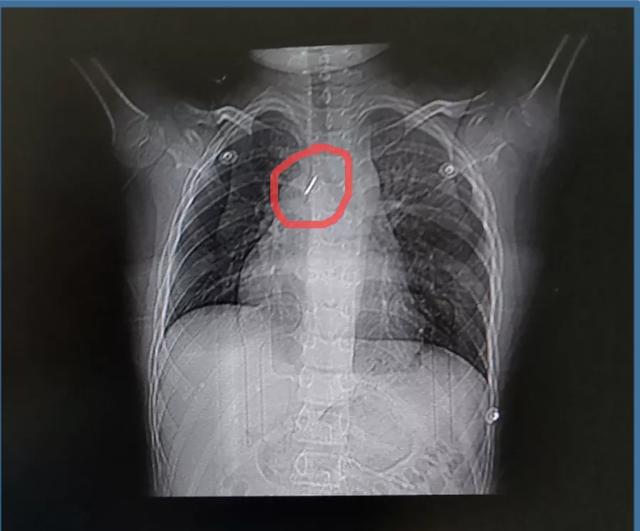

近日,9岁的男童牛牛(化名),在学校期间玩图钉,不慎吸入气管,出现胸闷及呼吸困难,当地医院行胸片及胸部CT证实异物在右主支气管,针尖朝上,有可能损伤气道,引起气管瘘等并发症,非常危险,被紧急转入新乡医学院第一附属医院。

△ 肺部CT提示右主支气管开口处有异物